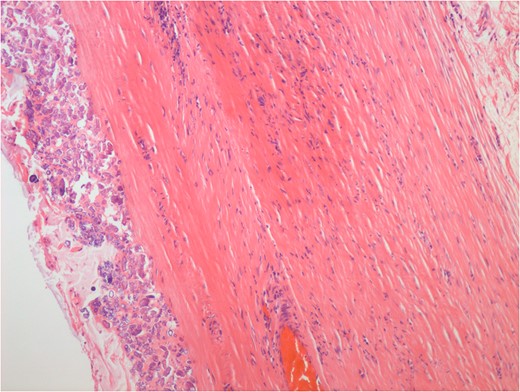

A 74-year-old female, with a background history of hypertension and hypothyroidism, presented to the emergency department with a 6-h history of sudden onset generalized abdominal pain. The pain was colicky in nature, associated with nausea and refractory to analgesia. Examination revealed tenderness in the right upper quadrant and epigastrium. Blood tests were normal except for a mild neutrophilia (7.5 × 109/l) and lactate of 2.5 mmol/l. A computed tomography (CT) scan of her abdomen and pelvis was performed which showed abnormal loops of small bowel along the right side of the abdomen with mesenteric fat stranding. A partially calcified structure was noted lying medial to the loops of bowel (Figs 1 and 2). The patient proceeded to have an explorative laparotomy performed. Intraoperative findings revealed an ischaemic loop of small bowel wrapped around a mass in the mesentery adjacent to the sigmoid colon (Fig. 3). The patient underwent a partial small bowel resection with primary anastomosis and en-bloc resection of the mass with the formation of an end colostomy. The final histological revealed a 6 × 4 × 4 cm cystic colonic duplication cyst separate but adjacent to the sigmoid colon. The inner lining of the cyst revealed mucinous epithelium, with mucin contained within. The wall of the cyst was sclerotic with occasional lymphoid aggregates, smooth muscle and neurovascular bundles (Fig. 4). The patient made a good recovery and was discharged home.

Haemolysin and eosin stain showing occasional lymphoid aggregates, smooth muscle and neurovascular bundles within the duplication cyst.